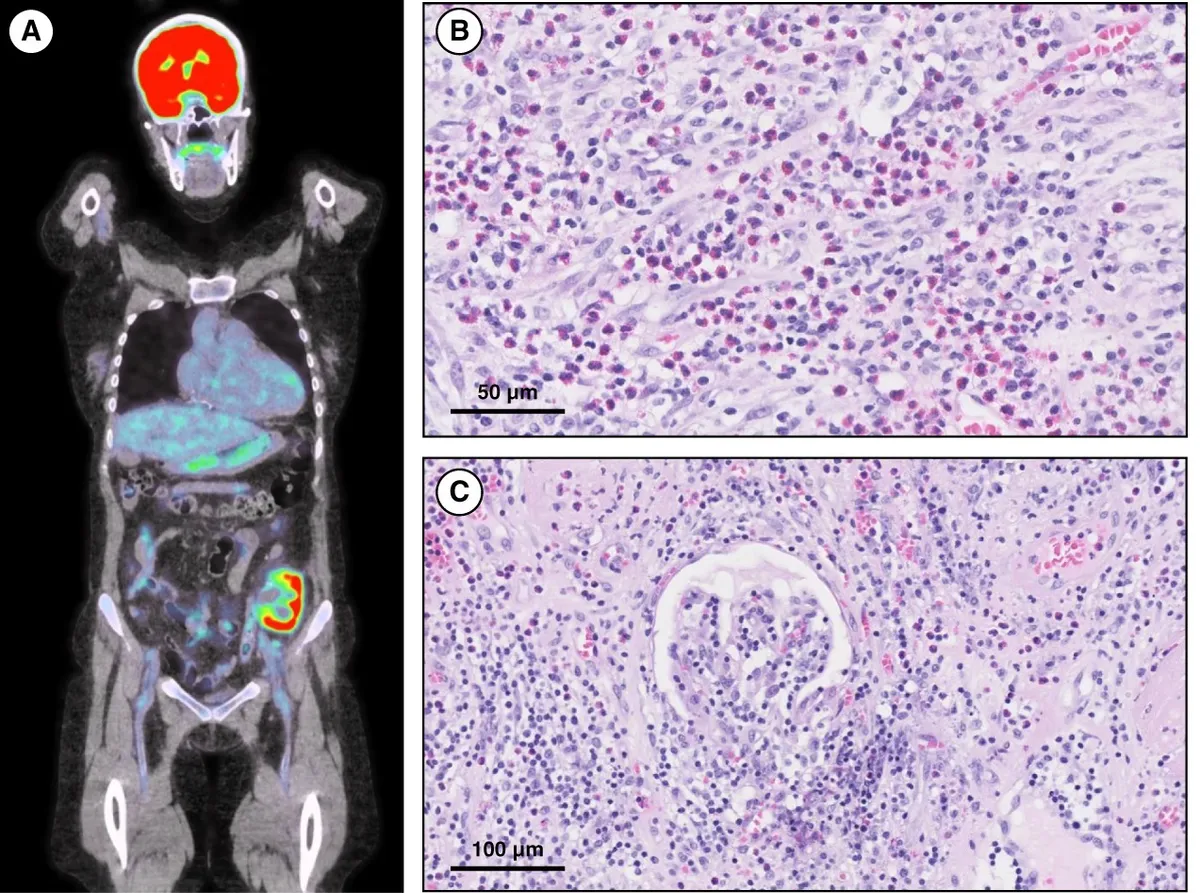

Uma causa incomum de hematúria glomerular intermitente!

Uma causa incomum de hematúria glomerular intermitente!

Hematúria pós infecção, caso clínicos para auxiliar no entendimento de causas glomerulares comuns e raras...